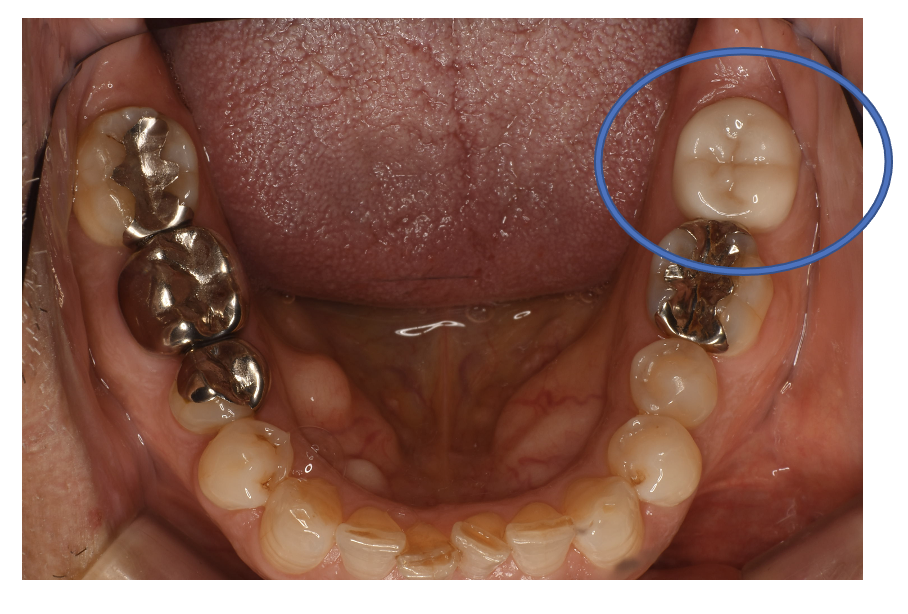

フルジルコニアCr 31 No.78

Before

After

| 治療方法 | フルジルコニアCr 虫歯などで失った歯質を天然歯と同じ色・質感のセラミックの一種であるジルコニア(人工ダイヤモンド)で補う治療法。 |

| 治療のデメリット | 変色がなく耐久性の高い治療ですが、歯周病や二次虫歯を予防するためには歯科医院での定期的なメインテナンスが大切です。 |

| 費用 | ¥89,000 |

| 通院回数 | 1ヶ月〜6ヶ月 |

| 備考 | 院長より 銀歯の内部に虫歯が進行してしまっていたケースです。中を開けて見てみると、外から想像するよりもはるかに虫歯が広がってしまっていました。幸運にも神経を保存できたので、生きた臓器としてまだ使うことが可能です。残存歯質がかなり薄く弱くなってしまったので、ジルコニアで被せて守ってあげています。しっかりとした治療ができたので、まだまだ長く使っていけるでしょう。 |